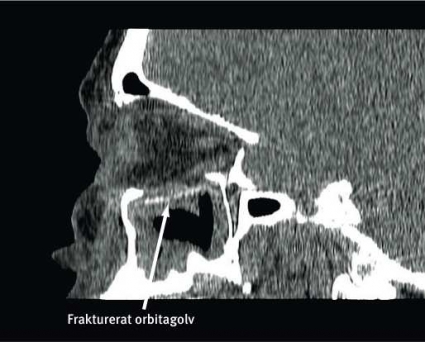

Noggrann klinisk undersökning är av största betydelse i utredningen och en förutsättning för att upptäcka och bedöma de olika komplikationerna, såsom fastklämd extraokulär muskulatur, bulbskada eller synnervsskada. Vid misstanke om fraktur ska ansiktsskelettet undersökas med datortomografi med tunna axiala snitt, och från de axiala snitten görs koronara och sagittala reformaterade serier. Avbildning av ögonhålan i dessa tre plan är nödvändig för diagnostik av orbitaväggsskador och för planering av rekonstruktionen. Tredimensionella bilder ger framför allt en bra visualisering av ansiktsfrakturer utanför orbitan och av implantat vid postoperativa undersökningar.

Kirurgisk rekonstruktion av orbitan syftar till att återställa orbitaväggarnas anatomi och orbitans volym. Vid blow-out-frakturer är rekonstruktion av orbitabotten vanligast, följt av rekonstruktion av orbitans medialvägg. Orbitabotten är inte en plan yta utan har en tredimensionell struktur som man bör återskapa vid rekonstruktionen. Orbitagolvets yta är konvex medialt baktill i ett område som kallas »posterior bulge«, medan den främre laterala delen av orbitabotten är skålformat konkav. Orbitagolvets mediala begränsning sluttar uppåt i 45 graders lutning för att möta den mediala orbitaväggen.

En 53-årig kvinna föll ner för en trappa, slog sig i ansiktet och ådrog sig högersidiga orbitafrakturer. Preoperativt fanns inget dubbelseende eller enoftalmus, däremot smärta i ögat vid blickriktning uppåt och lateralt. Preoperativ datortomografi visade en ren blow-out-fraktur av orbitabotten och medialväggen (Figur 2). Defekterna involverade större delen av orbitabotten ända bak till orbitans apex samt den mediala orbitaväggen upp till sutura frontoethmoidalis. Volymbestämning gjordes i mjukvaran Osirix efter att orbitans begränsningar markerats på alla axiala snitt mellan orbitans övre och nedre begränsning (60 snitt). Den skadade sidan uppmättes till 31,3 cm3, att jämföra med den friska sidans 26,0 cm3.